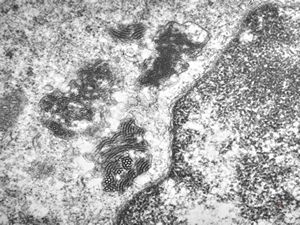

M,21y. | annulate lamellae - intracranial germinoma

M,21y. | annulate lamellae - intracranial germinoma